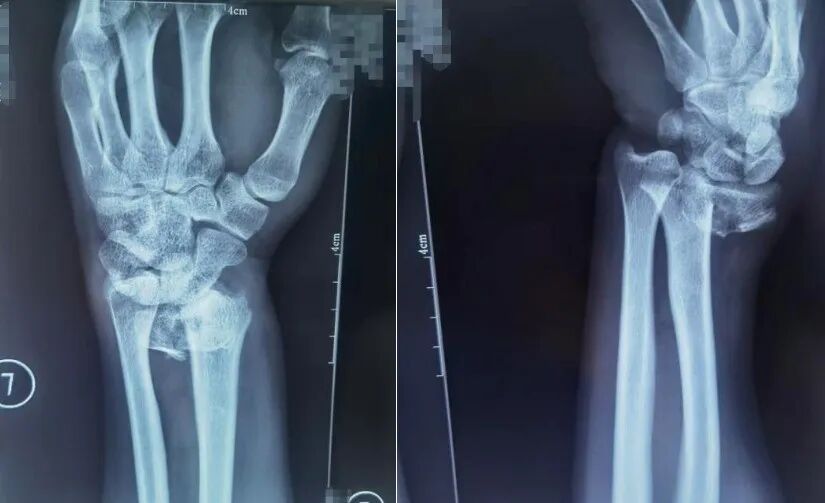

跌倒時用手腕撐地是常見的自我保護動作,但這一動作極易導致橈骨遠端骨折,表現為手腕腫脹疼痛、活動障礙,嚴重時還會出現明顯畸形。

患者橈骨遠端骨折,圖為復位前正位、復位前側位。圖源:哈爾濱骨傷科醫院